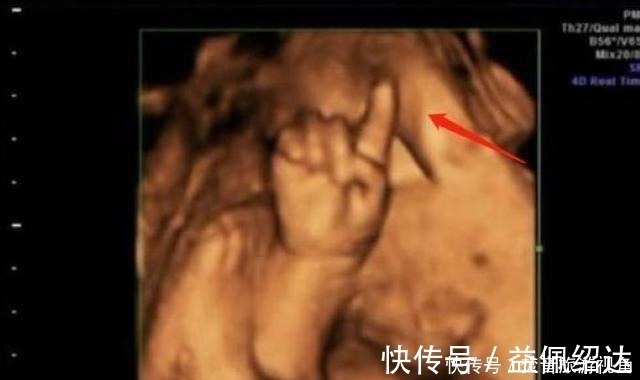

第一次做检查时,胎儿的脸部、身体都看得非常的清楚,让陈女士感到了很大的安慰。值得一提的是,孩子的一只手伸出了一个手指,非常的可爱。让人没想到的是,第二次检查时,孩子的手指伸出了两根,第三次手指变为了三根,最后一次检查,孩子的手指就变成了四根。

医生看到这种情况,也是非常的吃惊,他还调侃道:这孩子可是北大清华的料,可不能耽误人家,陈女士听后非常的开心。就这样,\\\\\\\"天才胎儿\\\\\\\"在网上迅速火了起来,他在子宫中掰手指算数成为了网友们新奇的谈资。